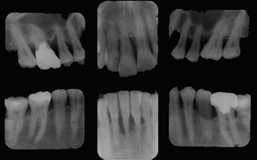

| 初診時パノラマ写真 | 10年後パノラマ写真 |

| 44歳 男性 | 上顎は、抜髄・Fop・連結固定により最長16年機能。 |

口腔内およびX線所見:

口腔内清掃状態は不良で、残存する全ての歯に動揺が見られるが、特に上顎では

残存骨量1/3以下で重傷度の歯周疾患進行状況である。下顎の歯槽骨破壊は約1/2。

処置および経過:

初期治療終了後、主訴である6│57を抜歯してブリッジ装着。

3-│-3については、特に骨吸収進行が著明であったので 歯周外科処置を行った

のちにブリッジを装着した。

下顎に関しては、4321│7 を抜髄の上、321 を連結固定を行い一旦治療を終了した。

メインテナンスには応じないものの、1年に1回程度の来院が続き5年を経過したころ、

有髄のままブリッジを装着したF6D│の歯槽骨吸収が著明となり抜歯。

また、残る4-│-6についても骨吸収の進行が認められたので改めて歯周外科処置

(HAP使用)を行った。

1982年 3-│-3 抜髄→Fop→連結固定

1989年 4-│-6 抜髄→Fop+HAP→連結固定

そののち、現在に至るまで、1月に1度のメインテナンスを欠かすことなく継続中。全体に予後良好。

但し、'92年(初診より10年後)に│46、'97年(初診より15年後)に4-│-3を抜歯して

現在は総義歯装着。抜歯の原因は、過重負担による歯牙破折と脱離に伴う二次カリエスであった。

考察:

欠損歯のない下顎が、初期治療とメインテナンスだけで16年間現状を維持し続けたのに対し、

治療は、初診時歯槽骨吸収が1/2以上あった上顎に集中している。

私の経験上、手術をしなければならない歯(歯槽骨吸収が1/2以上)は、10年・15年が限界だと

思っています。しかし、これらの経験を踏まえてより積極的な治療を取り入れている今の治療はもう

少し延命効果が高いとは思いますが、結果が出るのは10年以上先の話しです。